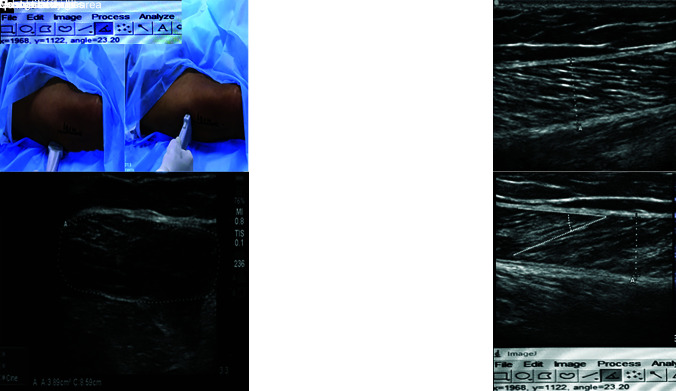

Patients and methods: We conducted a randomized, prospective, double-blind trial in which 30 patients mechanically ventilated for more than 48 hours and receiving enteral feed were enrolled. Patients were divided into two groups, and all patients received enteral feeds with total calories of about 25 kcal/kg/day. In the high-protein feed (HPF) group, patients were targeted to receive 1.5 gm/kg/day of protein, whereas in the standard feed (SF) group, patients received 1 gm/kg/day of protein. After ICU admission, muscle thickness, CSA, echogenicity, and PA were measured in all mechanically ventilated patients on days 1, 3, 5, and 7 using bedside ultrasound. The right lower limb vastus lateralis (VL) and the medial head of the gastrocnemius were investigated.

Abstract Image